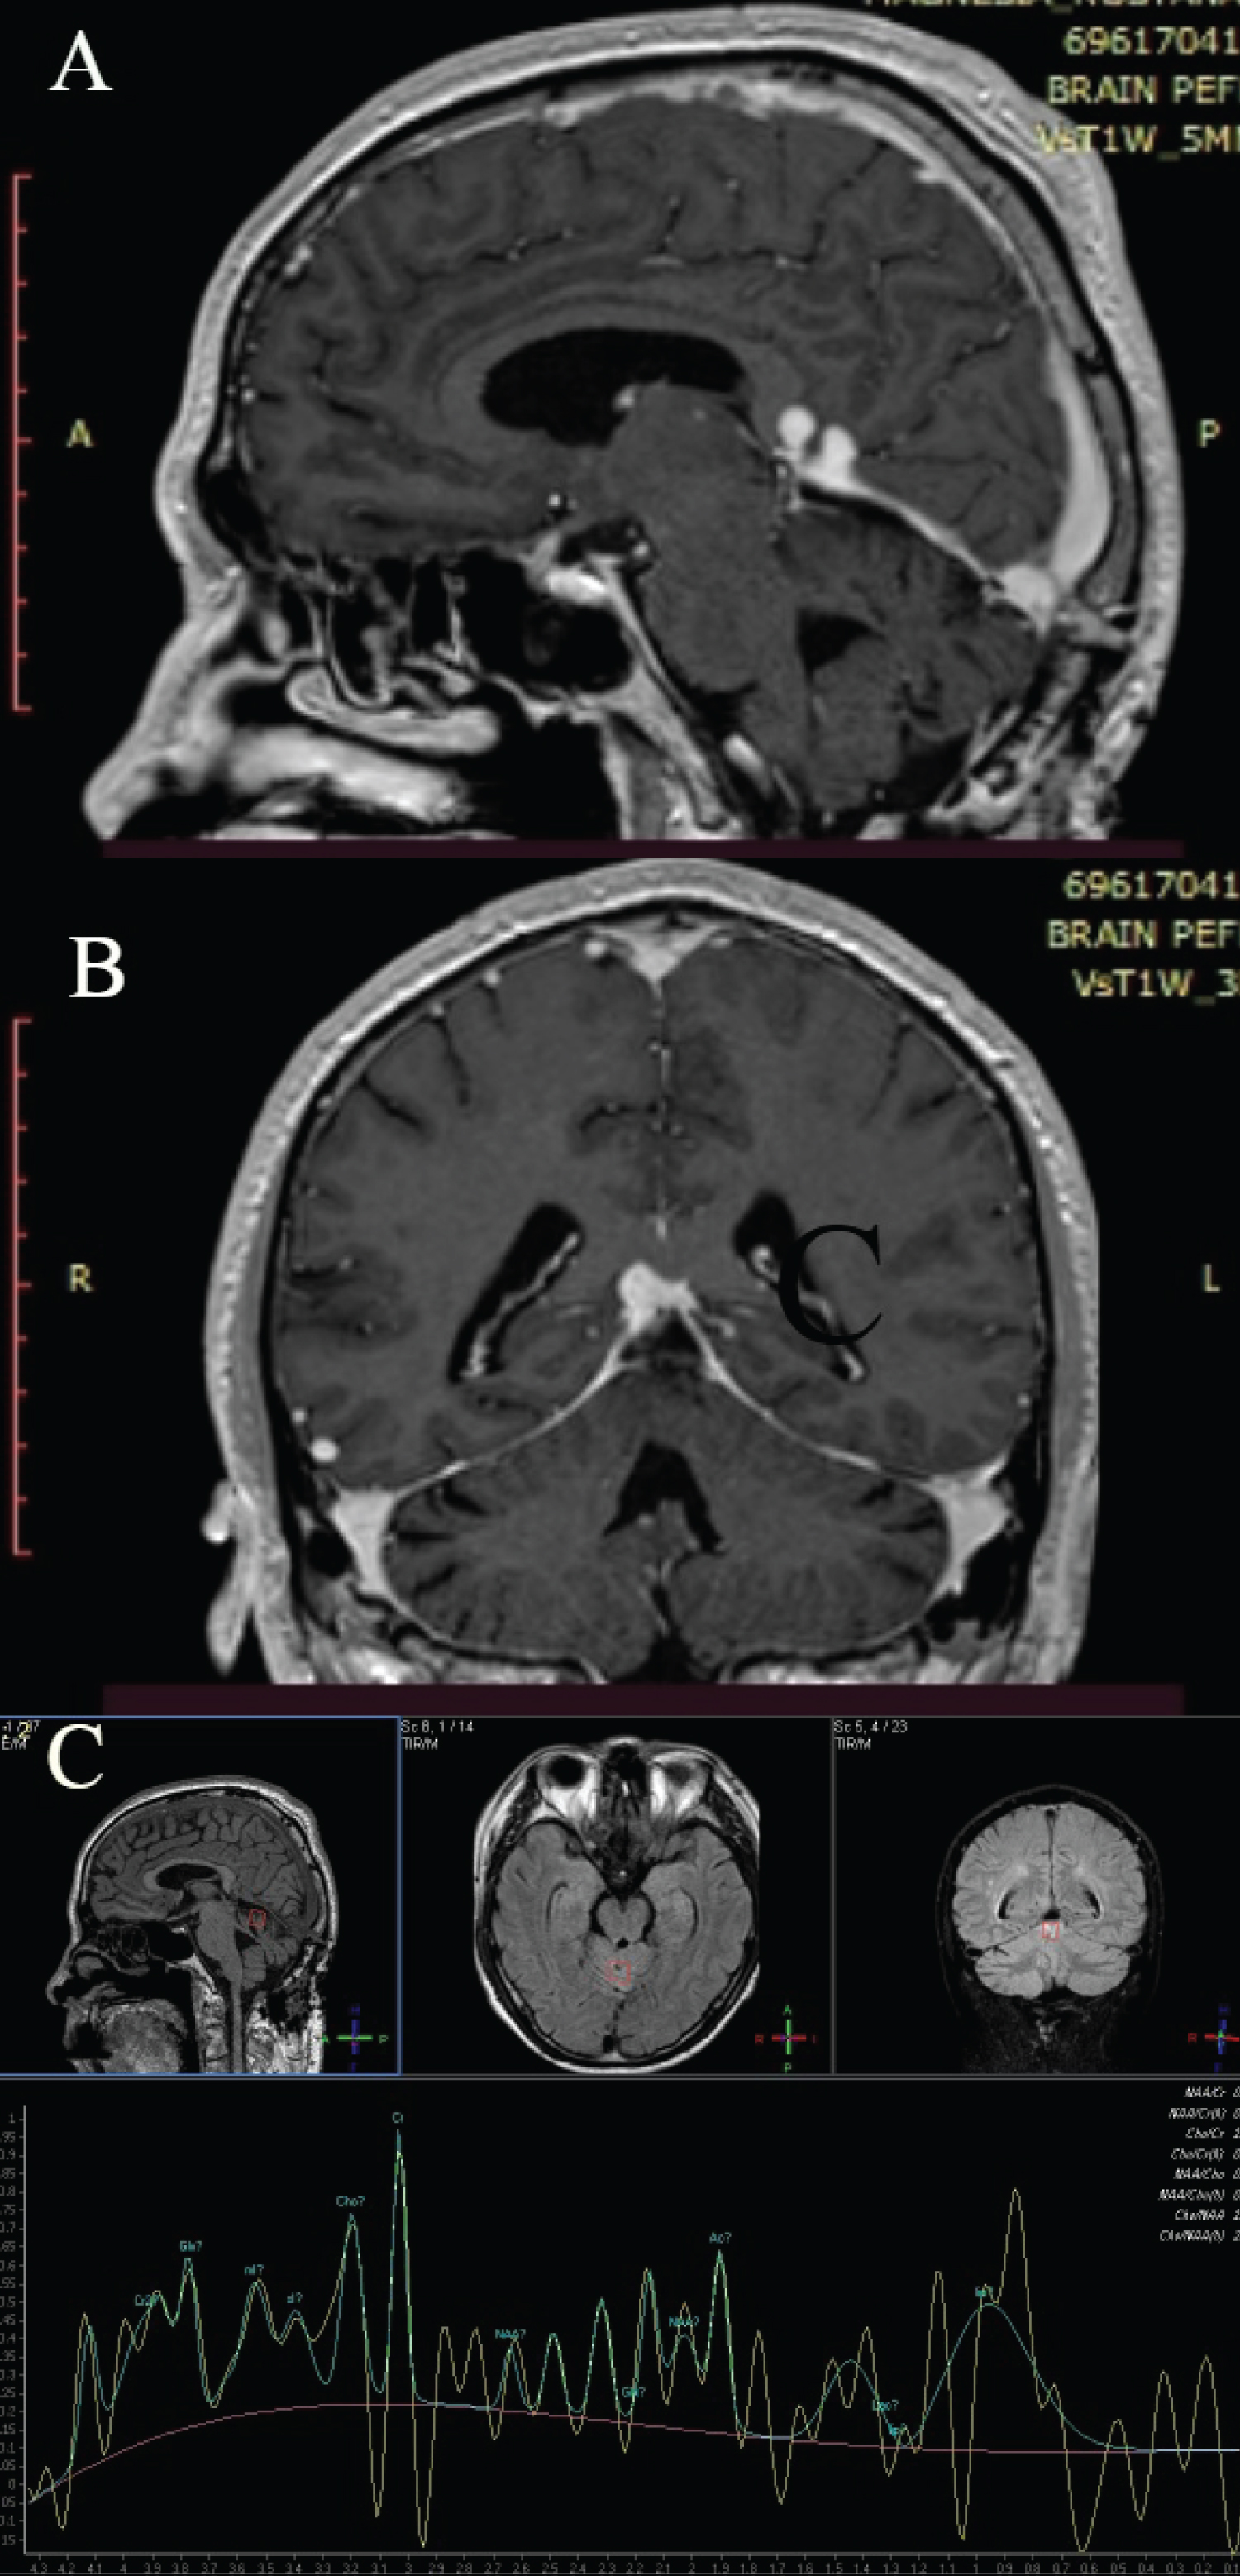

The patient had radiotherapy 3 months after the operation and had a postoperative MRI control 3 months after radiotherapy. The patient can hear and his behavior is adequate. There are sometimes problems with walking, which are becoming better in time. MRI shows that the postoperative corridor has no complications; there are no signs of tumor growth in the previous place, but there are supratentorial signs of tumor growth (Figure 4). The latest might be considered for Gamma Knife Radiosurgery at our hospital.

Figure 4: Postoperative follow-up. A) Sagittal T2WI image that shows supratentorial part; B) Coronal T2WI image; C) Conventional MR spectroscopy that shows increased creatinine. View Figure 4